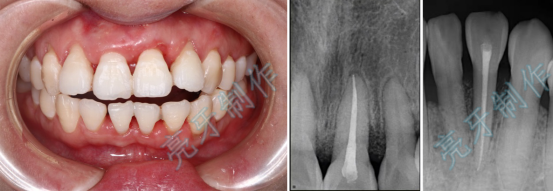

病例一:上门牙外伤,牙齿脱落;再植治疗3个月后,恢复良好。